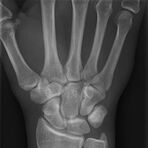

Röntgen Knochen

Röntgenaufnahme einer Hand

• Fraktur

• Arthrose

• Rheumatische Gelenkerkrankungen

• Degenerative Veränderungen der Wirbelsäule

• Knochentumor

• Osteoporose

• Therapiekontrolle nach OP am Skelettsystem

• Vollautomatische Erstellung von Ganzbein- und Ganzwirbelsäulenaufnahmen